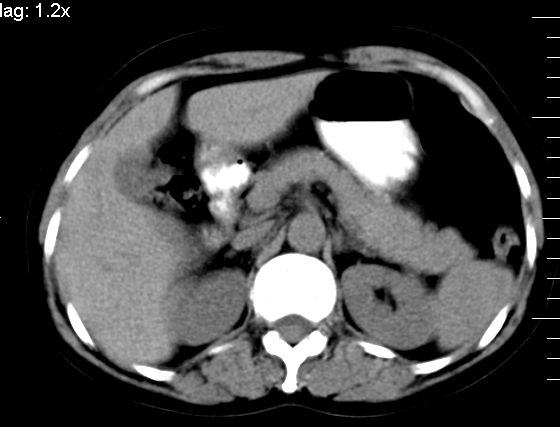

标题: CT10752:F,52岁,反复上腹部疼痛,平扫+增强. [打印本页]

f、52岁,反复上腹部疼痛2年。肺结核病史10多年,胸片双上肺结核纤维化。

ct表现:

肝大小形态未见异常,肝内外胆管无扩张,肝s8段见一动脉期明显血管样强化结节,门脉期呈高密度,延迟期呈等密度,胆囊不大,增强扫描见胆囊及胆囊颈管壁增厚,有强化。

双肾灌注良好,代谢增快,动脉期肾盂见造影剂,左肾下极背侧见一略低密度病灶,延迟期见似不强化囊肿,双侧肾上腺未见异常。

胰腺及脾未见异常。肾门水平腹膜后见小淋巴结。腹腔未见积液征象。

诊断:

1、胆囊炎(轻度)。

2、肝s8段结节,考虑小血管瘤。

3、左肾下极低密度灶,考虑囊肿可能性大,建议随访,除外小肾癌(无强化可以基本除外)。

4、目前ct表现尚不能解释患者上腹部疼痛,建议上消造影检查,除外胃炎等疾患。